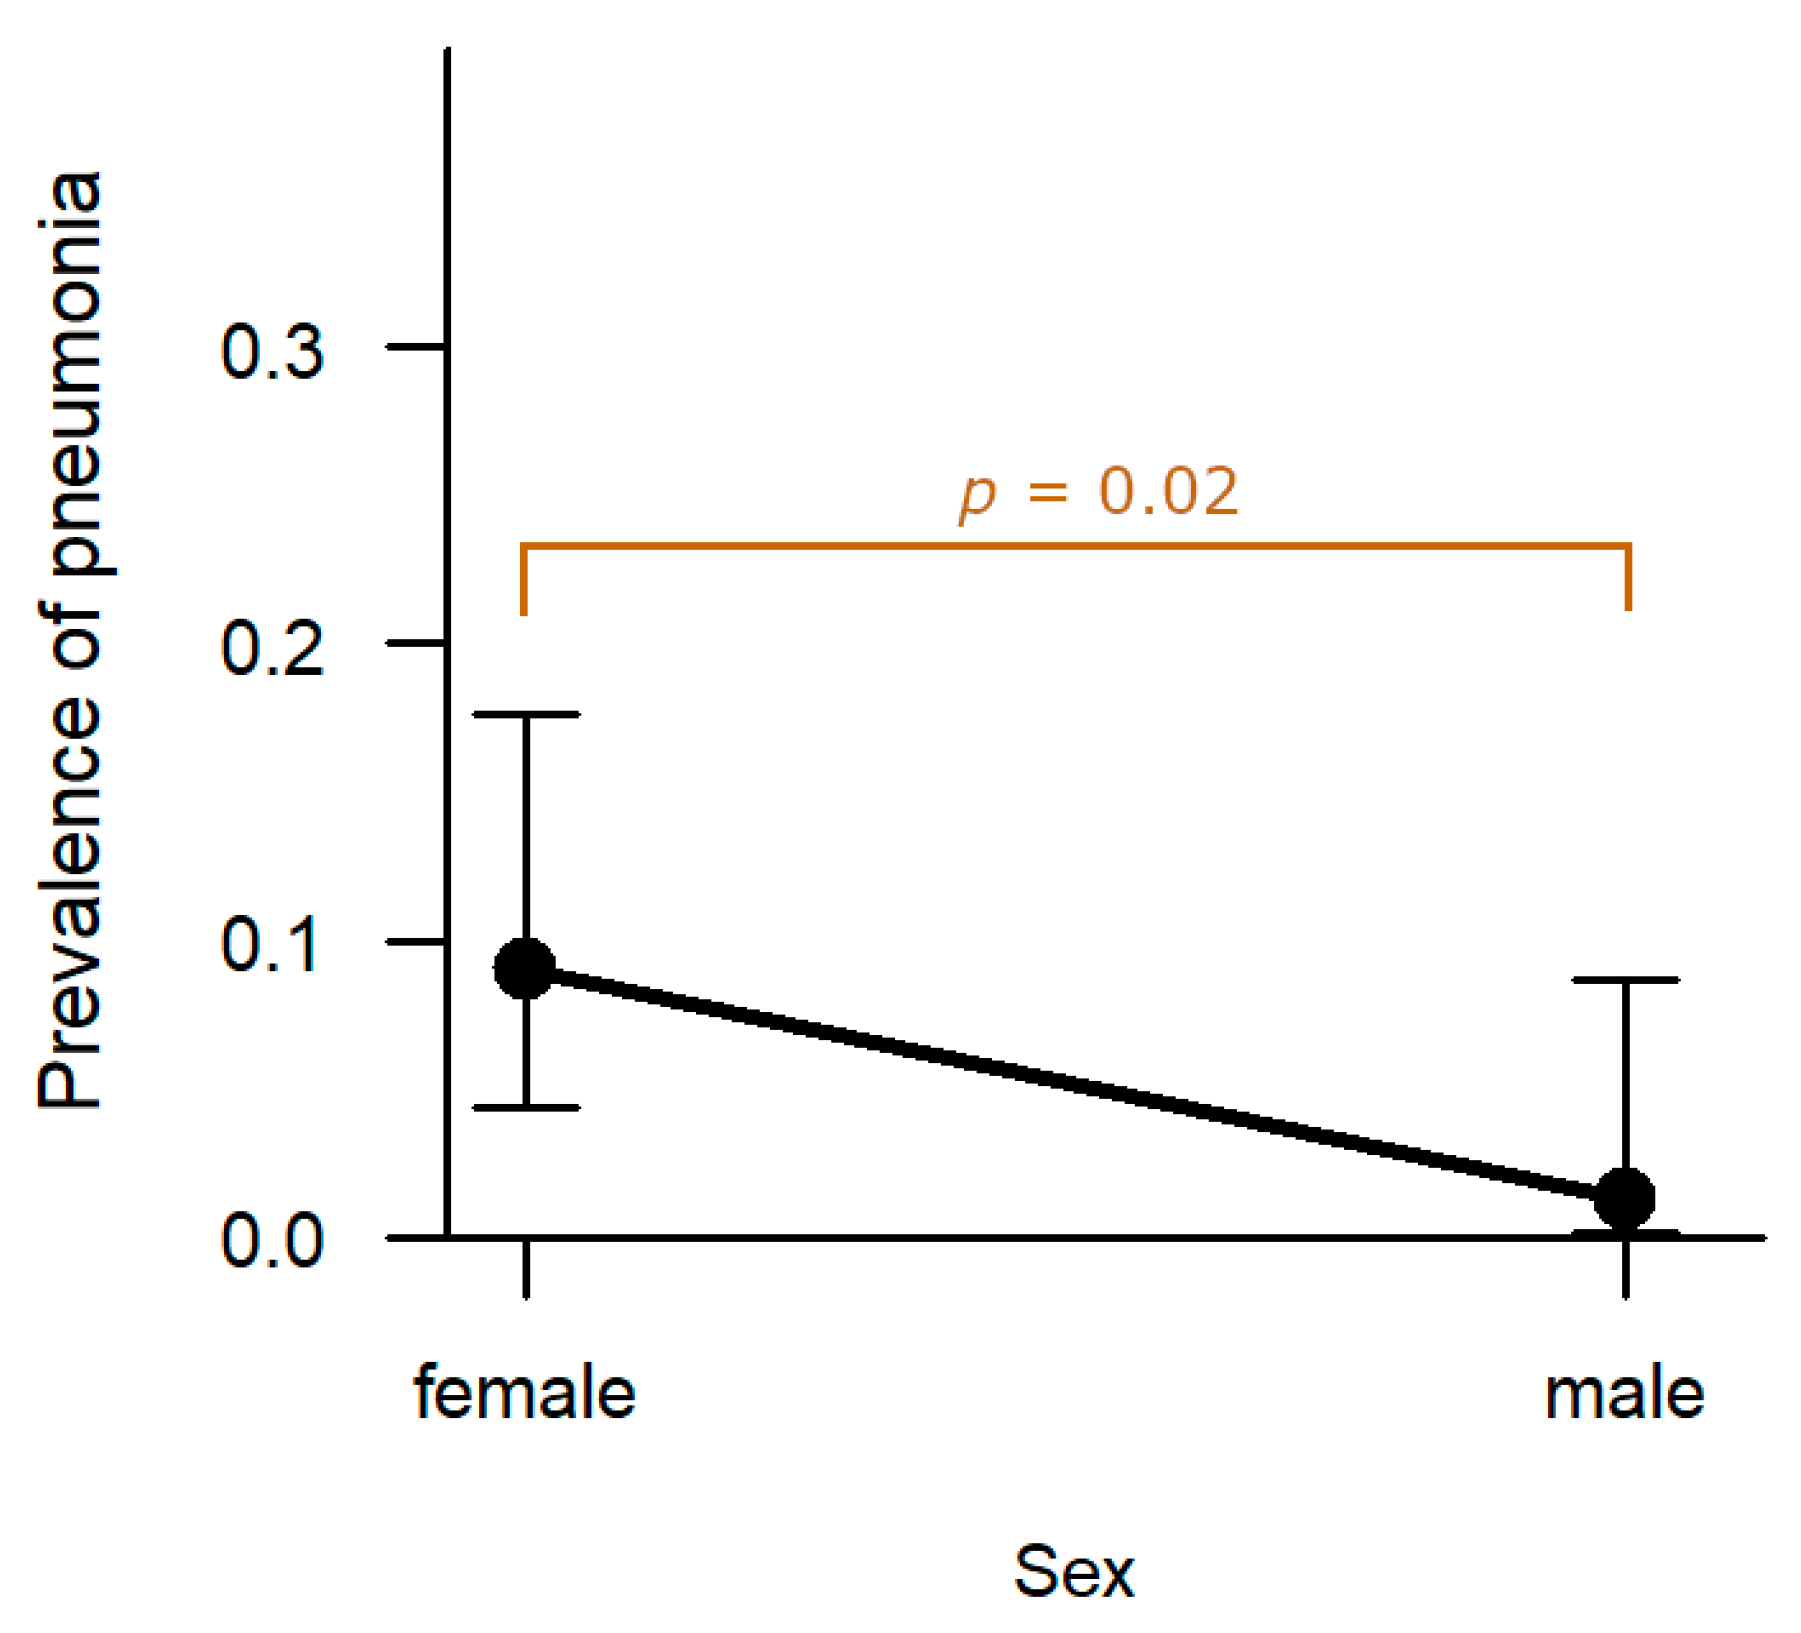

3.1.3. Respiratory System

Lung: In eight cases (5.2%), the hunted hares exhibited pneumonia. The prevalence in females (9.0%, n = 7) was significantly higher compared to males (1.3%, n = 1,

p = 0.022;

Figure 10). Age, hunting ground, and sampling year had no significant effect on prevalence of pneumonia.

Pneumonia cases were mainly non-purulent with infiltrates of lymphocytes, histiocytes and plasma cells (75.0%, n = 6). One hare additionally showed a chronic focal pleuritis associated with cestode infection. The remaining two cases were either purulent or granulomatous (12.5%, n = 1, respectively). The one hare with purulent pneumonia, revealed additionally hyperplasia of the bronchus-associated lymphoid tissue.

Regarding the pathomorphological finding pneumonia, a difference between sexes was detected with more females affected. Common infectious pathogens within

L.

europaeus causing pneumonia are lungworms or

Toxoplasma gondii (

Nicolle and Manceaux, 1908), but the first was not detected during this study, and the latter was not tested out specifically. Non-infectious causes should be considered as well but were out of the scope of this study. So, we could neither identify the aetiology of pneumonia nor the reason for the higher prevalence in females. However, with a comparably low prevalence in hunted hares during this study and even in deceased hares sampled in the same federal state [

43], this predominantly non-purulent type of pneumonia is of rather minor relevance for the health status of

L. europaeus in this region.